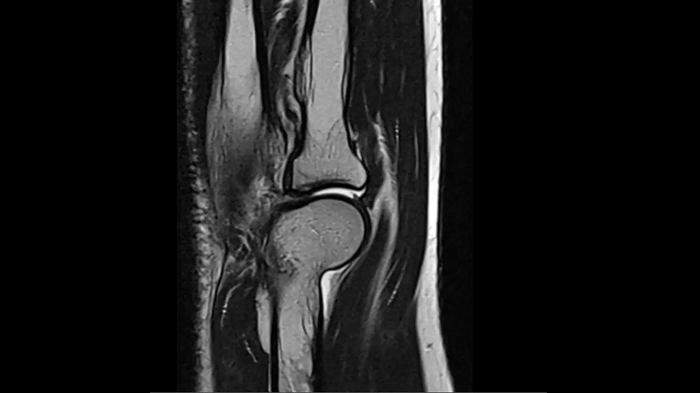

Knee

PD TSE Fat Sat with Deep Resolve and Simultaneous Multi-Slice

For clear imaging of the knee, outstanding fat suppression and performance are possible. Integrating the influence of Deep Resolve with the established Simultaneous Multi-Slice technique.

SMS 2 | Deep Resolve Gain & Sharp

0.4 x 0.4 x 3.0 mm2

TA 2:56 minutes

MAC-ID: 7aaaa0198. Image Credit: Siemens Healthineers

For clear imaging of the knee, brilliant fat suppression and performance are possible. Integrating the influence of Deep Resolve with the proven Simultaneous Multi-Slice technique.

0.3 x 0.3 x 3.0 mm2

TA 2:16 minutes

T1 SE

Outstanding T1 imaging of the knee using MAGNETOM Free.Star.

TA 2:54 minutes

3D MSK Imaging with Compressed Sensing

Knee imaging with T2w SPACE can be expedited using Compressed Sensing to reduce acquisition times, offering high-resolution images for uncompromised knee assessments.

Compressed Sensing 6

0.3 x 0.3 x 0.6 mm2

TA 4:15 minutes

MAC-ID: 7aaaa0175. Image Credit: Siemens Healthineers